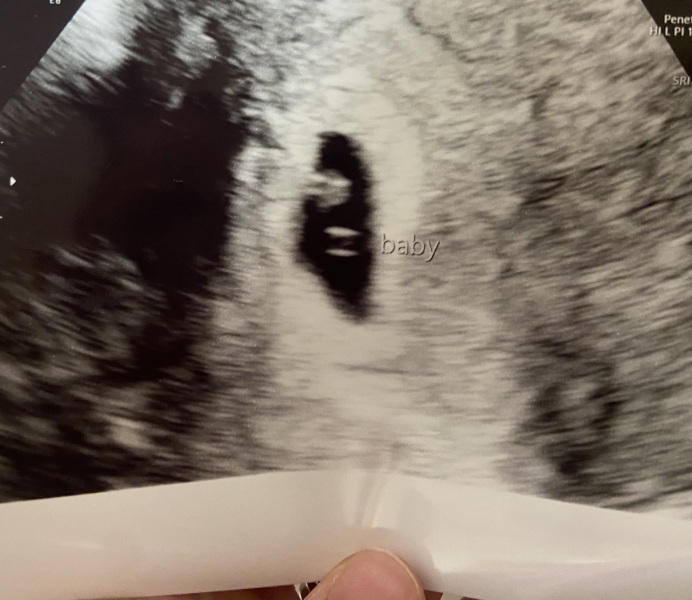

Good news at my EPU scan today, I’m around 6 weeks and baby had a heartbeat. They said everything is as expected. No clear cause of bleeding (which has now stopped) but I do have a cervical ectropion so it could be that. I also have the EPU number and can now self refer now I’ve been seen by them so that’s a relief too. It’s been a hard few days waiting for the scan (and the clinic today ran late which was excruciating). I’m over the moon everything is OK. I hope everyone else is doing well too x

@Emelene That is brilliant news, so pleased for you!! And how lovely to have seen the teeeeeeny baby already!

@Emelene that's absolutely wonderful news! So thrilled for you. And how lovely to have a picture of the little one already 💖

So so pleased for you @Emelene! Does it feel more real now that you’ve seen baby and heard a heartbeat? I still can’t quite believe I’m pregnant, it has always been something that happens to other people, not me!